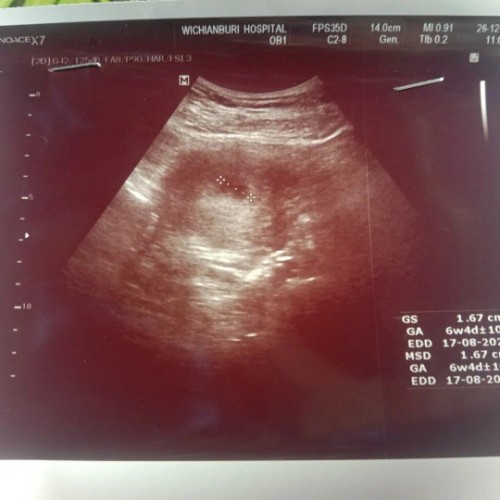

ขอดูใบซาวของแม่ แม่ 5-6 wk หน่อยค่า

ขอดูใบซาวของแม่ แม่ 5-6 wk หน่อยค่า เจอตัวน้อง กันหรือยังคะ บ้านนี้ไปซาวมาหมอบอก ยังไม่เจอตัวน้องเลย แอบกังวลค่ะ ท้องแรกท้องลม ไป กลัวเป็นเหมือนเดิมอีกค่ะมีแม่แม่คนไหนเคยท้องลมมาก่อนไหมคะ

พึ่งไปหามาวันนี้เหมือนกันคะ6w เจอแต่ถุงตั้งครรภ์ ไม่เจอตัวน้อง ท้องแรกก็ท้องลม แอบกลัวเหมือนกัน แต่ลุงหมอบอกว่าไม่ให้เครียดนะคะแม่ เดี๋ยวกลับไปเสียตังค์ซาวใหม่แล้วลุ้นให้เจอน้องอีกที ✌✌.

เคยท้องลมค่ะ ได้ขูดมดลูกไปเดือนกันยา 2565 ที่ผ่านมานึ่เอง ตอนนี้ตั้งครรภ์ใหม่ได้5วีค เจอแต่ถุงตั้งครรภ์อีกยังไม่เจอน้อง ตอนนี้กลัวมากๆเลยค่ะ หมอว่าซัก2สัปดาห์ค่อยมาซาวดูใหม่ กลัวจริงๆ

บ้านนี้ 5-6 w เจอน้องเล็กๆ มีหัวใจแล้ว ได้ยินเสียงหัวใจน้องด้วยค่ะ ตกใจเลย มาไวมาก 😅🥰 #ขอให้คุณแม่เจอน้องนะคะ

บ้านนี้เพิ่งซาวด์มา 6w2d เจอน้องตัวเล็กๆ 0.47 cm มีหัวใจเต้นแล้วค่ะ

6w6 ค่ะ เจอตัวเล็กมากค่ะ หมอยังไม่วัดคลื่นหัวใจให้ฟังเลยค่ะ